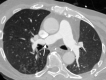

As lung transplantation has become the most effective definitive treatment option for end-stage chronic respiratory diseases, yearly rates of this surgery have been steadily increasing. Despite improvement in surgical techniques and medical management of transplant recipients, complications from lung transplantation are a major cause of morbidity and mortality. Some of these complications can be classified on the basis of the time they typically occur after lung transplantation, while others may occur at any time. Imaging studies, in conjunction with clinical and laboratory evaluation, are key components in diagnosing and monitoring these conditions. Therefore, radiologists play a critical role in recognizing and communicating findings suggestive of lung transplantation complications. A description of imaging features of the most common lung transplantation complications, including surgical, medical, immunologic, and infectious complications, as well as an update on their management, will be reviewed here. Keywords: Pulmonary, Thorax, Surgery, Transplantation Supplemental material is available for this article. © RSNA, 2021.